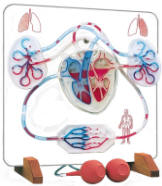

| Human Body Circulatory System -

| The muscular heart

pumps blood out through tubes or vessels, called arteries. These

branch repeatedly into microscopic capillaries that joint to form veins

that carry the blood back to heart. Our anatomical models begin

with an overview of the Circulatory System and even include functional

models. Next comes the arteries that carry the blood. The